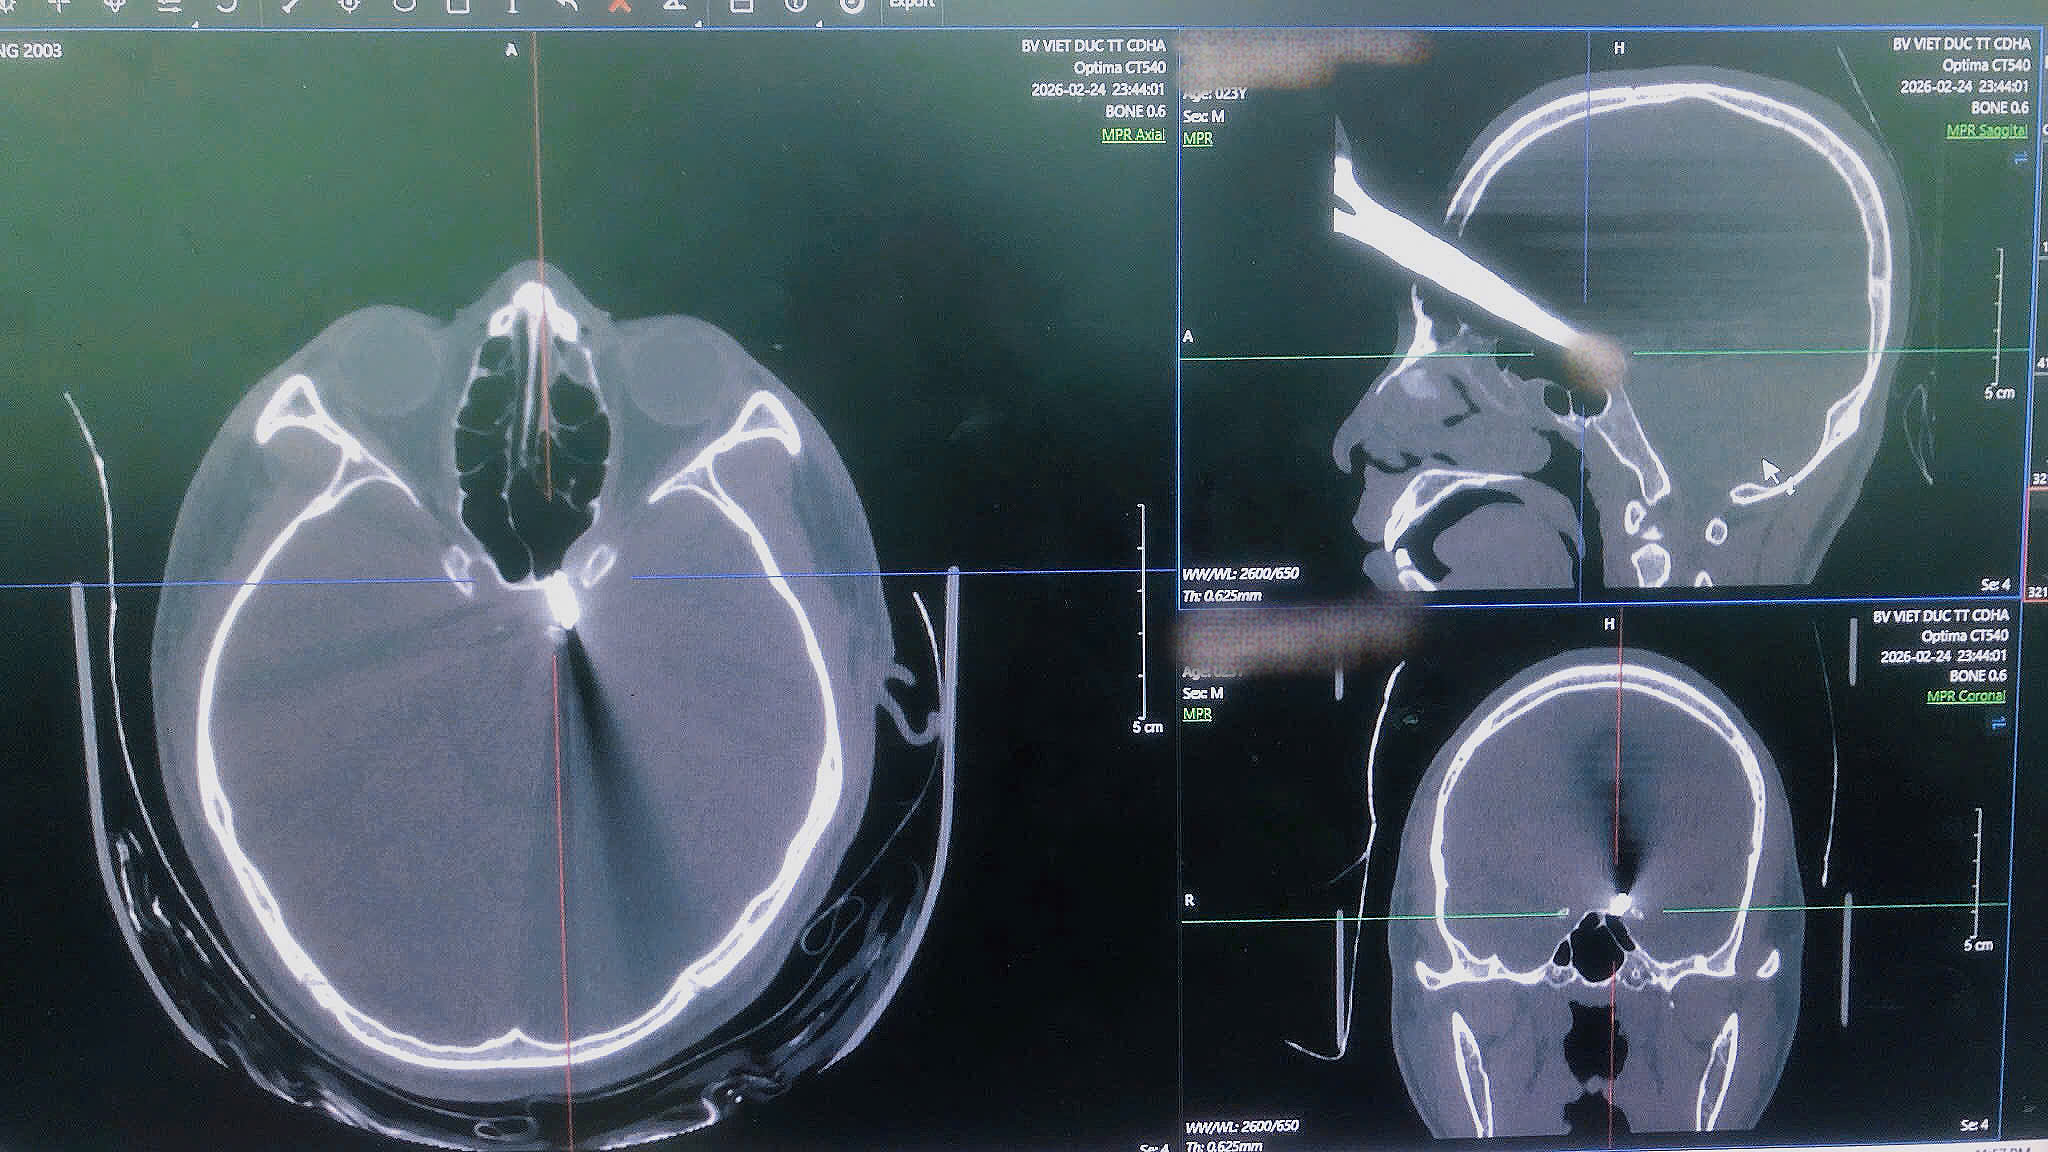

Hình ảnh phim chụp CT phát hiện dị vật.

Người bệnh được đánh giá nhanh tình trạng tổn thương, thực hiện các cận lâm sàng cần thiết. Kết quả chụp cắt lớp vi tính đa dãy cho thấy đầu nhọn của dị vật (kéo) nằm sát động mạch cảnh trong bên trái, chưa loại trừ tổn thương mạch.